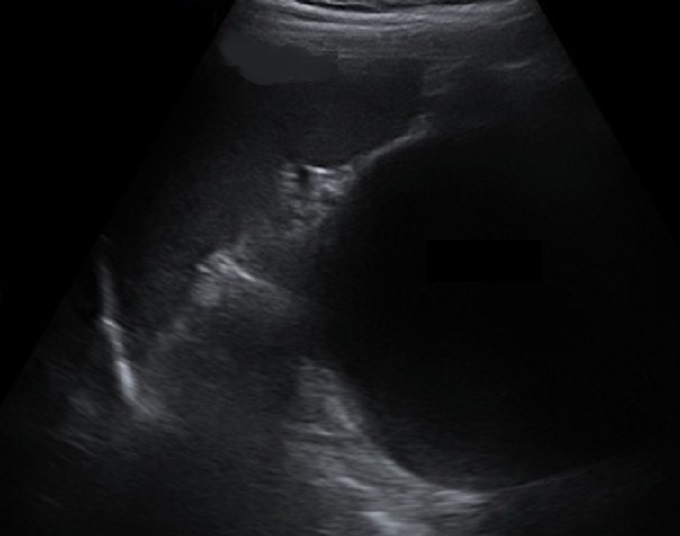

Image echographique d'une

pseudo-kyste du pancreas . La kyste est tres

volumineuse , aechogen a bord lisse , fine avec cône

de acoustique posterieure |